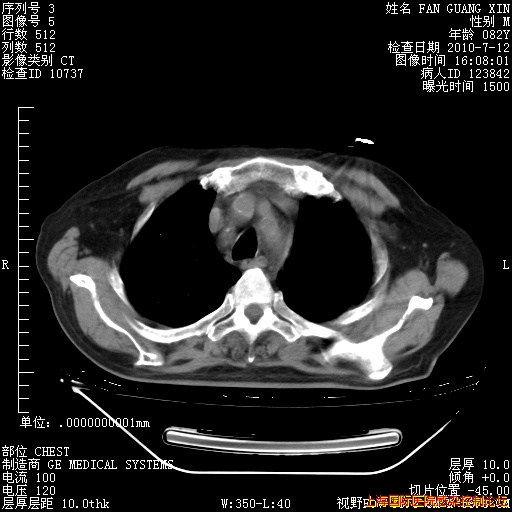

6月12日纵膈窗

今天CT

整整相隔30天的肺部CT好像有所好转啊。甲强龙减量第3天,需要观察体温。

海管,自昨日你和我通完话后,不知您岳父消化道症状有无缓解?体温怎样?阅读7.12日胸部ct,个人认为目前激素治疗是有效的,甲强龙减量是适宜的。因在抗痨治疗,需密切观察肝功、肾功能和血常规。不过,老年、长期住院和大量使用激素,很担心菌群失调发生